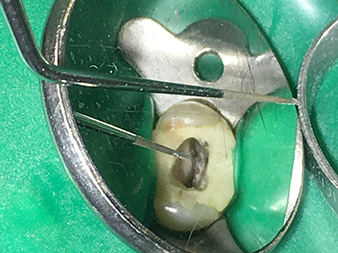

Efficient and atraumatic root canal treatment

Long-term conservation of dentition is the prime objective of modern endodontics.

Alongside efficient diagnostics and treatment methods, the use of the latest technical aids and instruments also makes an important contribution to successful patient care. Dr Shahrad Nouraie Ashtiani and his team at the practice in Bremen, Germany, treat up to ten endodontics cases a week. Patients’ desires for treatment which is as atraumatic as possible combined with good prognoses for success present a daily challenge for the dentist and oral surgery resident specializing in endodontics.

As an avid user of the expanded W&H instrument range for ultrasonic endodontics, Dr Nouraie Ashtiani is not only able to perform root canal treatments more efficiently but also to do so in a way which puts less strain on the patient. The dental expert masters even the most difficult of situations with ease. In a recent interview, the specialist in endodontics told us about the particular features which characterize the W&H instruments and mentioned possible risks which can arise in root canal treatment.

©Pictures: Dr. Shahrad Nouraie Ashtiani, Bremen